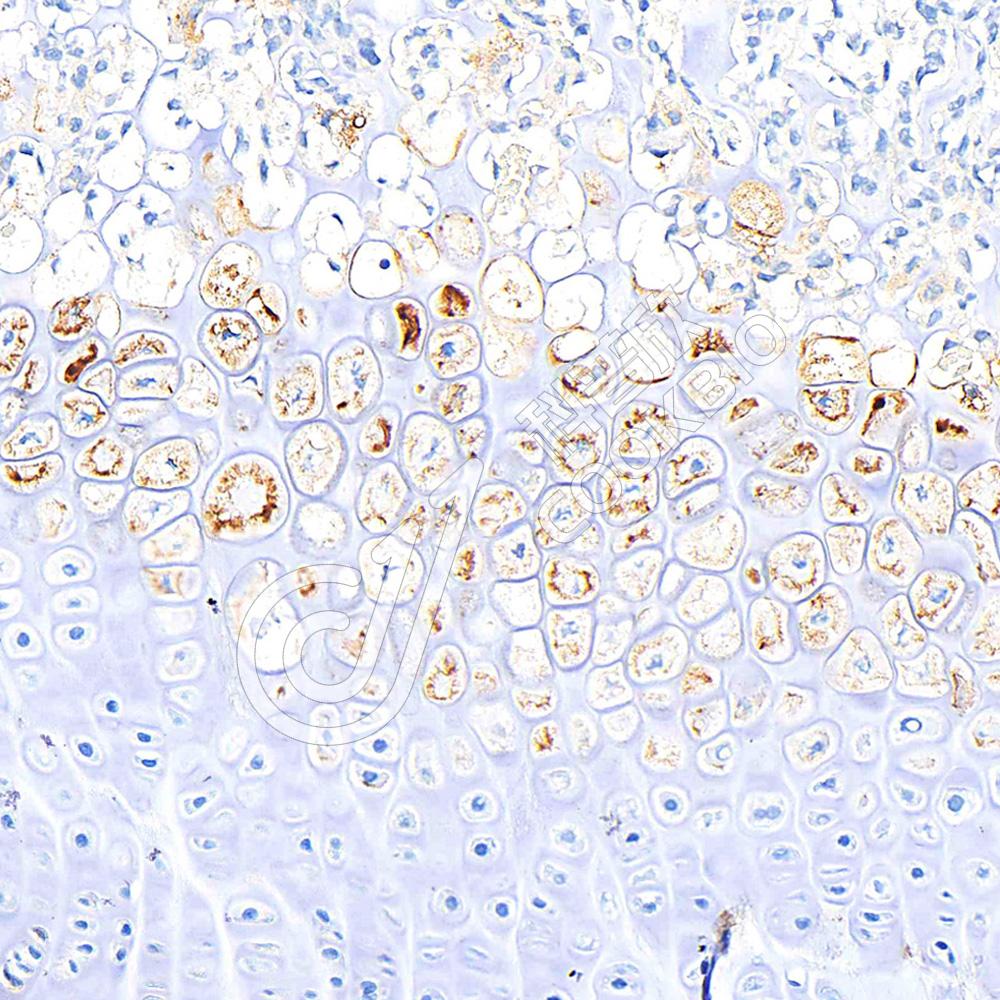

IHC检测Aggrecan蛋白(货号 K1347061).

样品: 小鼠软骨, 4%多聚甲醛 (货号KSG1101) 固定12-24小时.

抗原修复: 柠檬酸抗原修复液(干粉, pH 6.0) (KSG1201), 98℃, 20分钟.

—抗: 1: 800稀释, 4℃ 孵育过夜.

二抗: S-vision免疫组化多聚二抗(山羊抗兔),即用型 (货号KB3906), 室温孵育20分钟.

样品: 大鼠软骨, 4%多聚甲醛 (货号KSG1101) 固定12-24小时.